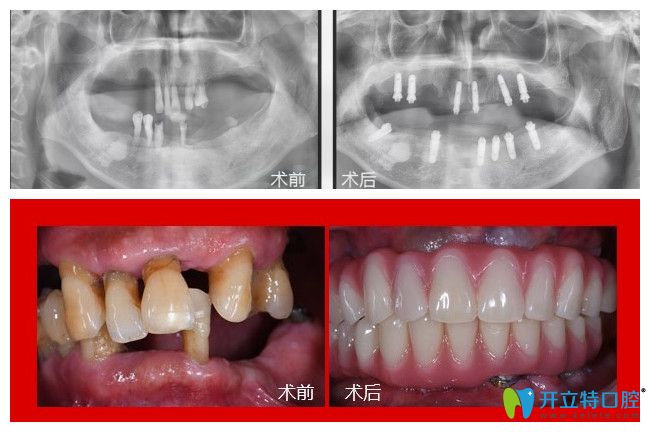

廣州廣大口腔67歲歐叔在廣大口腔用高齡精準(zhǔn)種技術(shù)解決了下半口缺牙問(wèn)題

67歲歐叔在廣大口腔用高齡精準(zhǔn)種技術(shù)解決了下半口缺牙問(wèn)題

恭喜67歲歐叔在廣大口腔用高齡精準(zhǔn)種技術(shù)解決了下半口缺牙問(wèn)題,關(guān)于60歲老人種牙好不好,我們來(lái)看看他的親身體會(huì)。